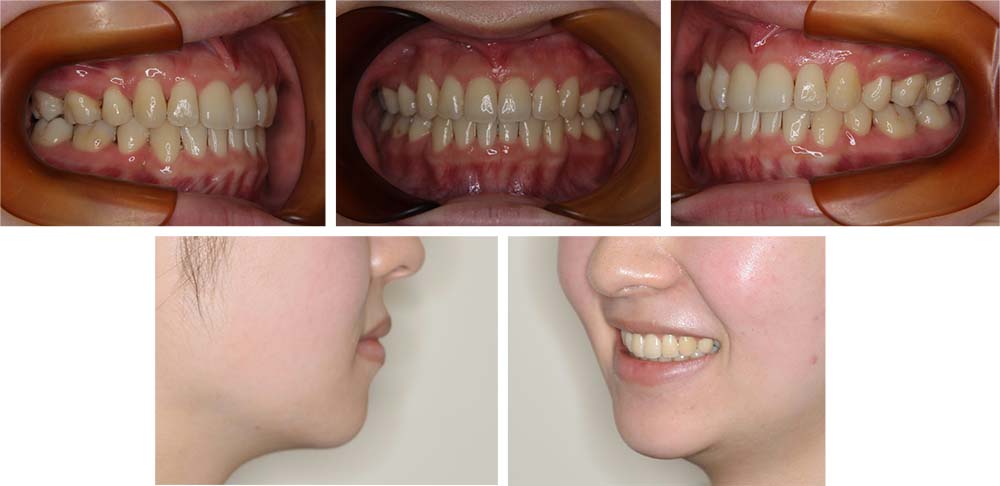

上顎左側側切歯の口蓋側転位を主訴としてご来院いただいた。初診時ご相談時には口元に対しての要求はなかったが、口元の突出(俗にいうゴボ口)とガミースマイルについての説明をしたところ、治療対象とすることを希望された。セファログラムの分析の結果、上下顎前突と診断した。上下顎小臼歯抜歯を行っていただき、矯正用アンカースクリューを併用し唇側マルチブラケット装置を使用して動的治療を行った。上下顎前歯の後退が十分行われ口元の突出感も改善した。上口唇はE-ラインから2㎜後退し、下口唇もほぼE-ライン上へ後退させ美しい口元の形態とすることができた。また、前歯の後退方向にも工夫を行ったことから、ガミースマイルについても軽減した。動的治療期間2年2カ月間。

治療前

治療後